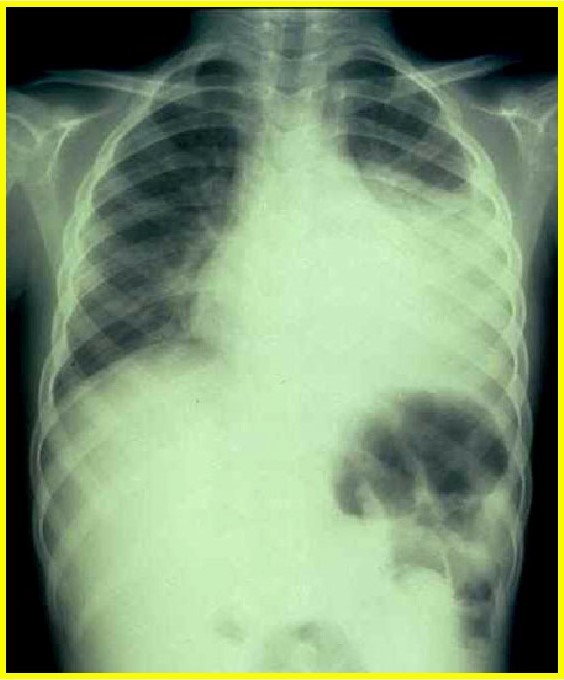

The initial symptoms of Legionnaire’s disease that occur

2-10 days after exposure are _____. They can progress to a _____ pneumonia.

The necrotizing pneumonia of advanced Legionnaire’s disease deomonstrates _____ consolidation, _____, and a “_____” appearance